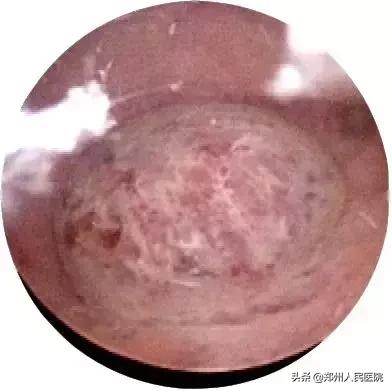

宫腔镜下常见的稽留流产合并宫腔异常图像

孕囊布满微血栓

术后宫腔图片

宫腔镜下宫腔组织吸引术,能精准的清除稽留流产组织,减少对子宫内膜的损伤,进而减少宫腔粘连的发生概率。另一方面对宫腔形态、子宫内膜进行全面检查,及时发现宫腔内病变:子宫内膜息肉、血栓、子宫畸形、子宫内膜炎等等,进一步治疗,避免同样的问题再次发生。